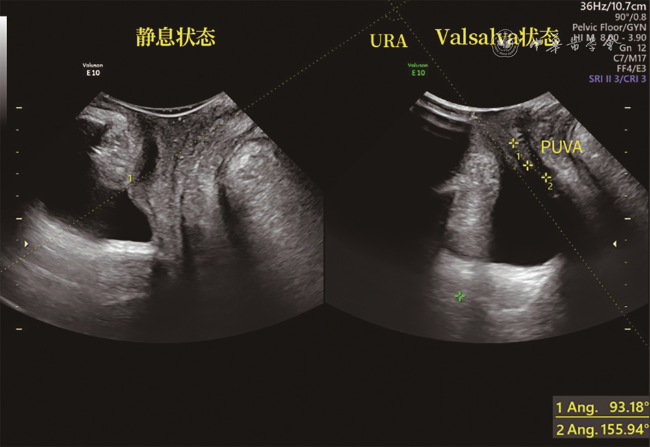

一般临床资料中,PFD组产次及新生儿体质量均值均高于对照组,差异均有统计学意义(P均<0.05),2组年龄及体质量指数比较差异均无统计学意义(P均>0.05);正常对照组和PFD组盆底超声参数BND、PUVA、URA、COD、RAD及LHA比较,差异均有统计学意义(P均<0.05,表1图1, 2, 3)。

注:URA为尿道旋转角度,PUVA为膀胱尿道后角